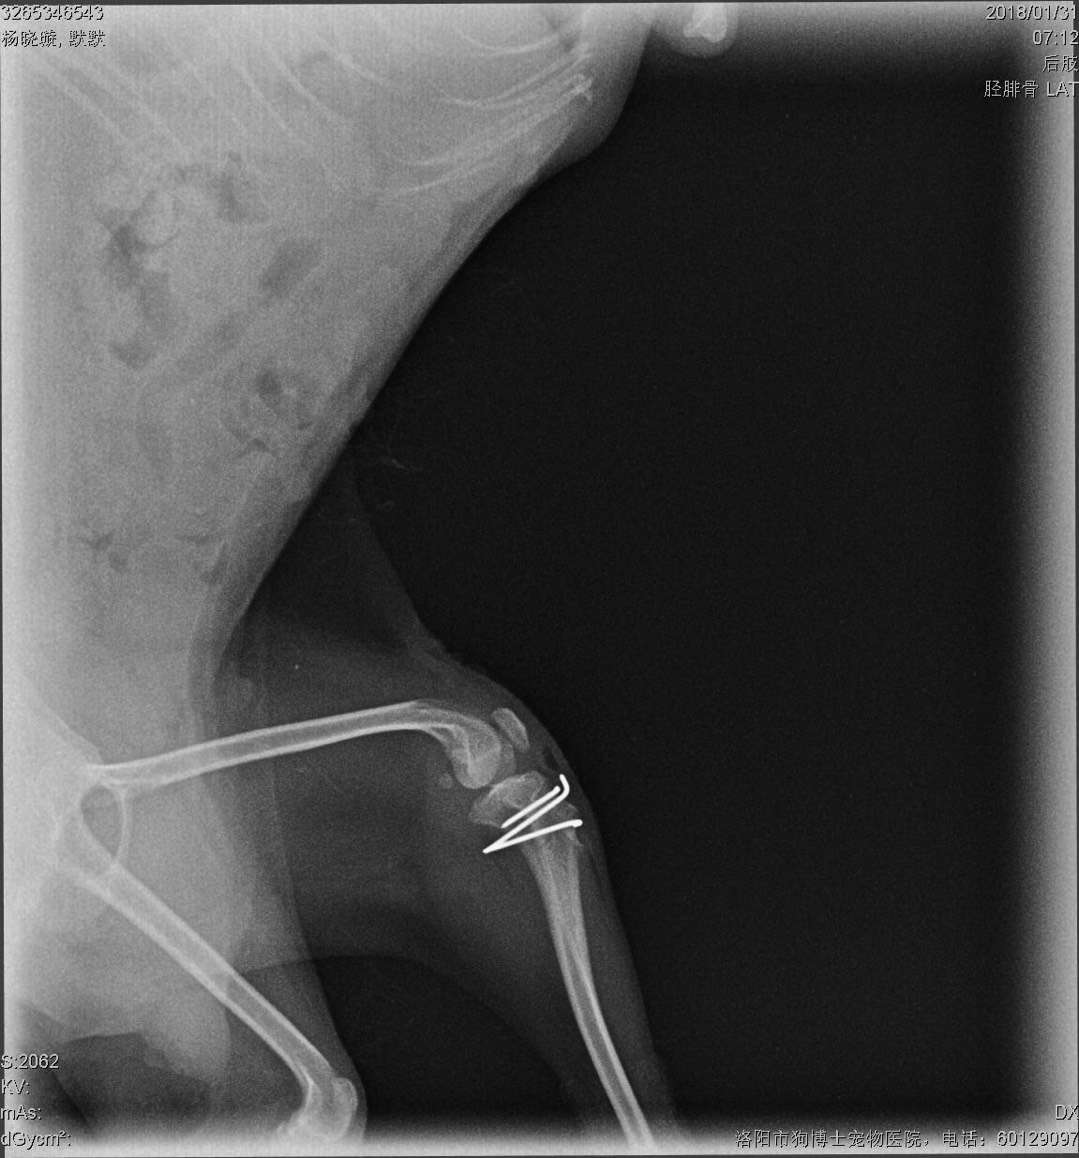

微茶髕骨移位手術一例:微茶妹妹,雙側(cè)髕骨3級移位移位,同時實施滑車溝再造術、脛骨粗隆移位術、及髕骨周圍軟組織修復術。手術期間,呼吸麻醉,心電監(jiān)護,手術持續(xù)2小時,一切順利,住院護理中。